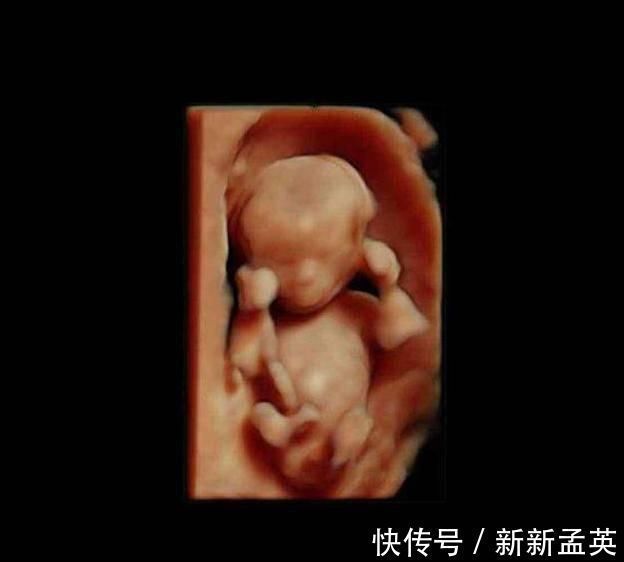

进入第10周,胎儿的发育更细致了,比如眼睛和眼睑已经融合,眼睛清晰可见,手臂和胳膊等都很清楚,此时的胎儿开始发阿玉生殖器官,不过肉眼是看不出来性别的。